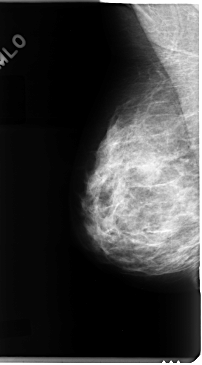

C_0091_1.RIGHT_MLO

RIGHT_MLO LINES 4744 PIXELS_PER_LINE 2624 BITS_PER_PIXEL 12 RESOLUTION 50 NON_OVERLAY